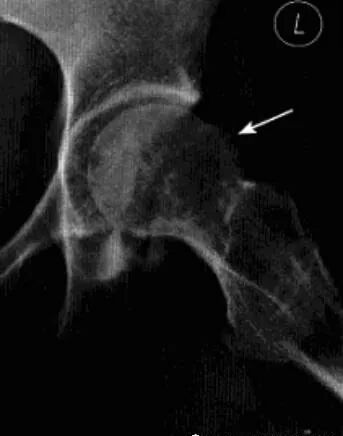

髋关节撞击综合征

也称股骨髋臼撞击综合征,是由于股骨近端和髋臼盂缘间解剖的异常,或解剖正常但长期不正常外力作用于髋关节,导致两者长期不正常接触、碰撞,产生反复的微型创伤致使关节盂缘和关节软骨退变,从而引起慢性髋关节疼痛及髋关节屈曲和内收受限的疾病。分为凸轮撞击和钳夹撞击两个类型。

病理:股骨头软骨呈明显退变现象,关节唇骨化、瘢痕化、体积增大、软骨下撕裂。

临床表现:凸轮撞击多见于喜欢运动的青年男性,钳夹撞击多见于活动较多的女性。典型表现为腹股沟区疼痛,通常在活动或久坐后加剧,呈间歇性,后期呈持续性。病变常呈单侧性,查体时髋关节活动受限,撞击试验阳性。

影像诊断:X线平片是基本检查方法,直立骨盆正位及髋关节侧位片。

平片:①凸轮撞击型,正位片示头颈连接处扁平,呈“左轮枪柄”样畸形,侧位片示股骨头颈凹陷减少,*边缘角变小<16度,②钳夹撞击型,髋臼窝过深,髋臼后倾,呈相交8字征,偏心距缩短<9mm。

CT:三维CT可测量股骨头颈连接处前外侧偏移量减低,股骨头颈联合处前上缘可见骨性突起。

MRI:股骨头颈凹陷减少(α>50°),股骨颈宽度与股骨头半径比率增大,髋臼后倾。盂缘退行性改变,撕裂、囊肿,关节间隙后期出现狭窄,周围肌肉炎症。